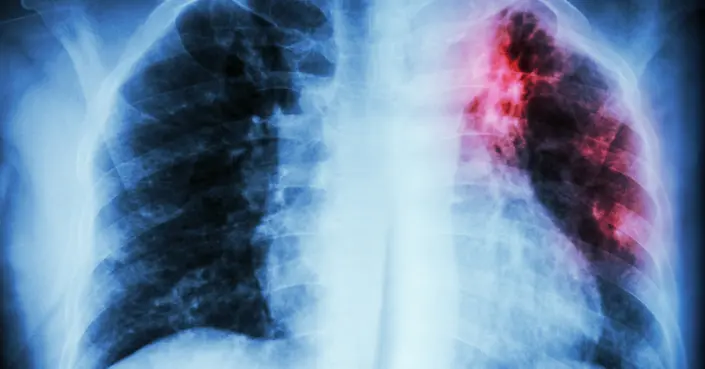

- الأشعة السينية: تساعد في تحديد مدى انتشار المرض وتأثيره على العظام أو الأعضاء الأخرى.